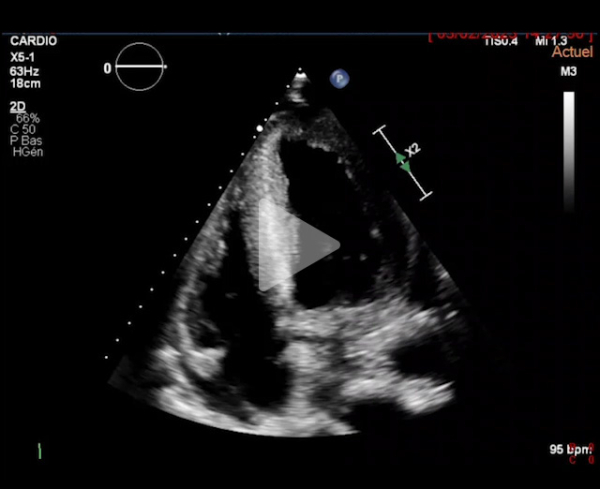

L'ETT montre :

- Dilatation modérée du VG. FEVG à 30%

- Cardiopathie hypertrophique sévère excentrique

- Flux mitral restrictif

- Ventricule droit non dilaté

- Paroi libre épaissie

- Minime épanchement péricardique circonférentiel

Vidéo 2